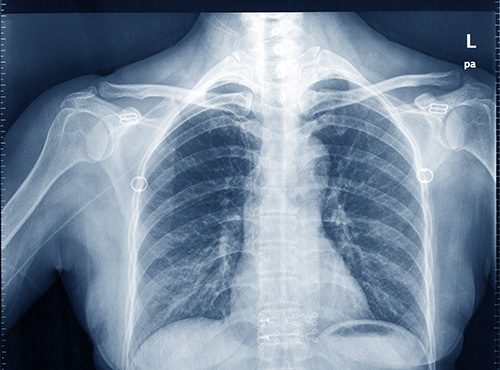

周元华回忆道,该名病患当年在体检时发现癌症指标异常升高,起初却始终找不到病灶。在他的建议下进行肺部X光检查,才惊觉已是肺癌四期且癌细胞扩散。面对年仅不到40岁的噩耗,周元华当时给出了一个关键的饮食建议:“回想过去常吃的食物,现在统统戒掉;以前不爱吃的,现在立刻开始吃。”